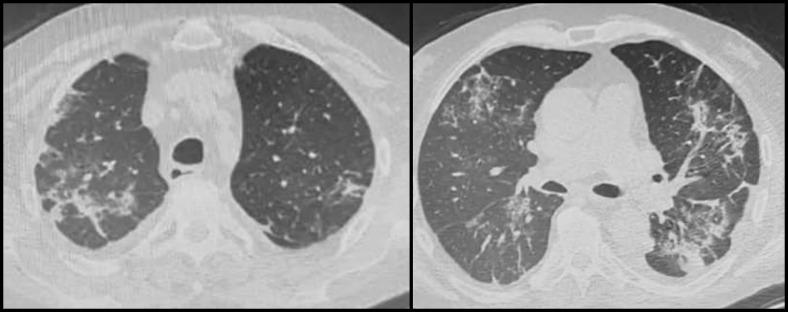

From March 17 to April 23, 2020, a total of 143 kidney transplant recipients were contacted. Twenty-eight patients needed in-hospital consultation for problems unrelated to COVID-19, 3 of whom needed hospitalization. Eleven patients were managed at home for mild urinary or respiratory diseases, and 1 was referred to the hematologist. We identified 2 suspected cases of COVID-19 infection, and the patients were referred to hospital care. Immunosuppressive therapy was modulated, and intravenous corticosteroids and potentially effective antiviral therapy were administered with a favorable outcome.

2020年3月17日至4月23日,共联系了143名肾脏移植受者。28名患者因与COVID-19无关的问题需要住院咨询,其中3人需要住院治疗。11名患者因轻度泌尿系统或呼吸系统疾病在家中接受治疗,1名患者被转诊至血液科医生处。我们发现了2例疑似COVID-19感染病例,并将患者转诊至医院治疗。调整了免疫抑制治疗方案,并给予静脉注射皮质类固醇和可能有效的抗病毒治疗,结果良好。